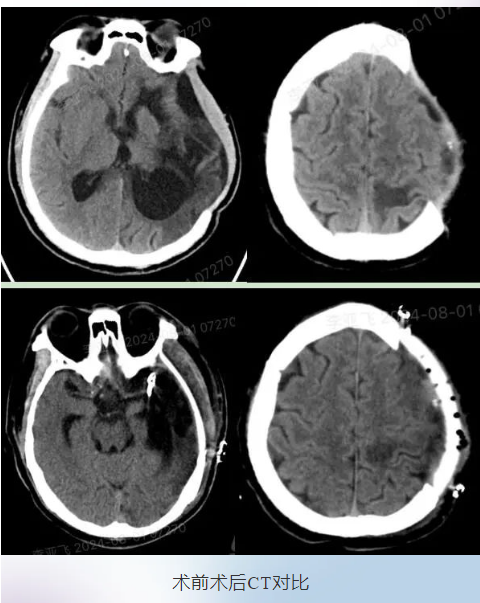

手术过程顺利,术后复查CT。修补材料与骨窗贴合紧密,外观与对侧基本对称且无皮下积液等问题。经过医护人员精心治疗及心理疏导,张先生照着镜子,摸着自己的头,再也不是一个大“坑”了,他露出了满意的笑容。